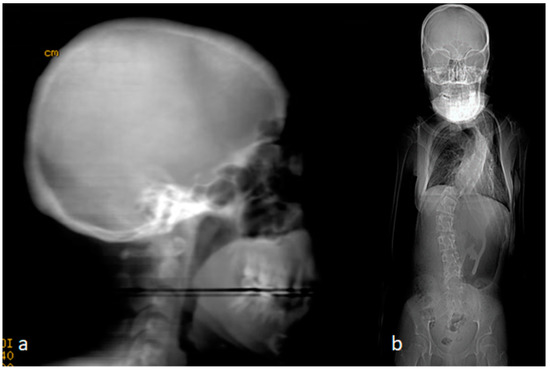

The clinical examination of the parents revealed a very interesting outcome. The mother showed a typical clinical and radiological phenotype, as seen in her two offspring. She manifested marfanoid habitus associated with craniosynostosis. The mother was 40 years old and showed a similar typical clinical phenotype as her two siblings. A 3D reformatted skull CT scan showed totally fused metopic, coronal, and sagittal sutures, which resulted in very easily palpable ridges over the synostosed sutures. There was a noticeable disproportion between the cranium and the facial bones. In other words, this disproportion between the cranial and facial bones’ growth resulted in a huge difference because of the overgrowing of the facial bones on account of the cranial bones (Figure 3a). The reformatted skeletal phenotype CT scan of the mother showed a typical marfanoid habitus, long and thin limbs, long trunk and large cranium, macrognathia, and cervico-thoracic scoliosis of 70° Cobb’s angle. In her adolescence, her scoliosis did not respond to corset treatment and she refused surgical intervention to re-align her spine (Figure 3b) (please refer to Table 1).

Figure 3. (a,b). A 40-year-old mother with the typical clinical phenotype of her two siblings. A 3D reformatted skull CT scan showed totally fused metopic, coronal, and sagittal sutures which resulted in very easily palpable ridges over the synostosed sutures. There was a noticeable disproportion between the cranium and the facial bones. In other words, the stoppage of the cranial bone growth resulted in a huge difference from the overgrowing of the facial bones (a). The reformatted skeletal phenotype CT scan of the mother showed typical marfanoid habitus, long limbs, long trunk, small cranium, large facial bones, macrognathia, and cervico-thoracic scoliosis of 70° Cobbs angle. In her adolescence, her scoliosis did not respond to corset treatment and she refused surgical intervention to re-align her spine (b).